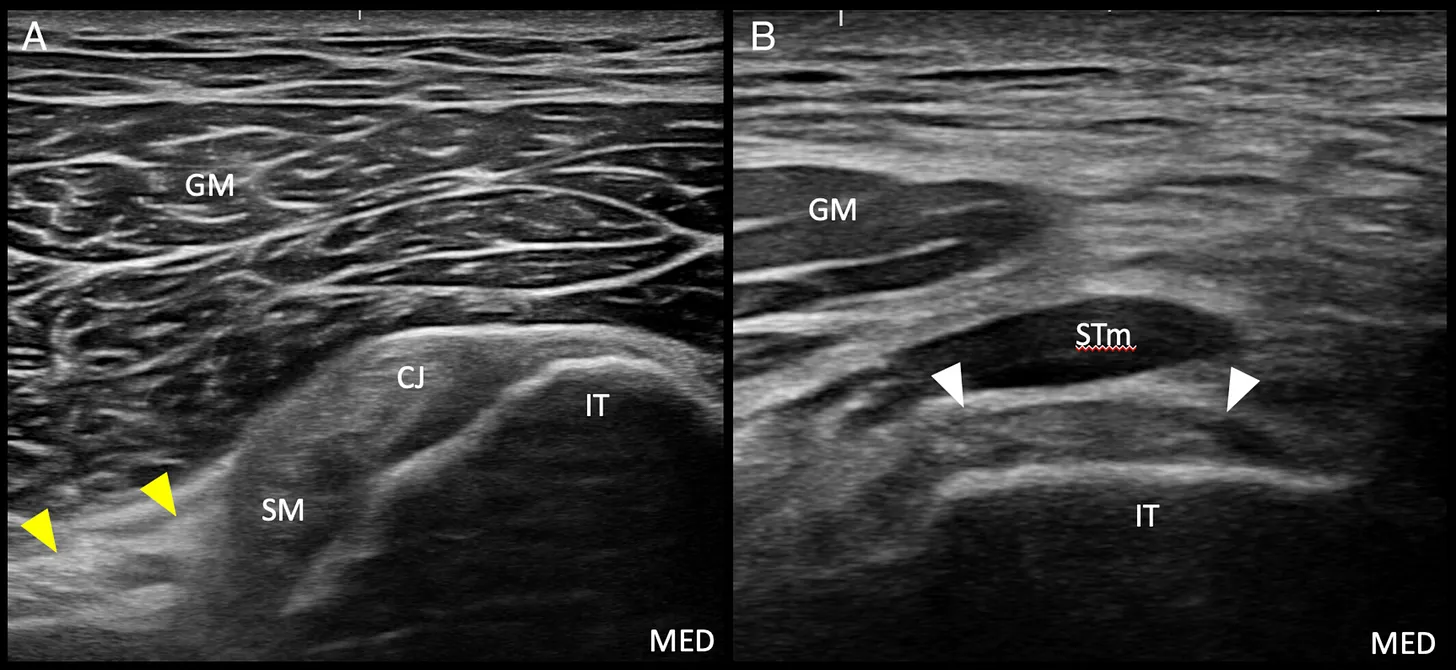

A. Posición anatómica del transductor ecográfico para la visualización en eje corto del tendón proximal del aductor mayor.

B. Imagen ecográfica en corte transversal del tendón proximal del aductor mayor (puntas de flecha). El músculo semitendinoso (STm) se sitúa superficial al tendón de origen isquiocondíleo del aductor mayor.

C. Preparación cadavérica que muestra la posición del transductor para la obtención de la imagen del tendón proximal del aductor mayor en eje corto.

IT: tuberosidad isquiática;

GM: músculo glúteo mayor;

MED: medial; PROX: proximal;

rectángulo: posición del transductor.

A. Posición anatómica del transductor ecográfico para la visualización en eje largo del tendón de origen isquiocondíleo proximal del aductor mayor.

B. Imagen ecográfica en vista longitudinal del tendón de origen isquiocondíleo proximal del aductor mayor (puntas de flecha). El aspecto medial del músculo semitendinoso (STm) se sitúa superficial al tendón de origen isquiocondíleo del aductor mayor.

C. Preparación cadavérica que muestra la posición del transductor para obtener la imagen en eje largo del tendón de origen isquiocondíleo proximal del aductor mayor.